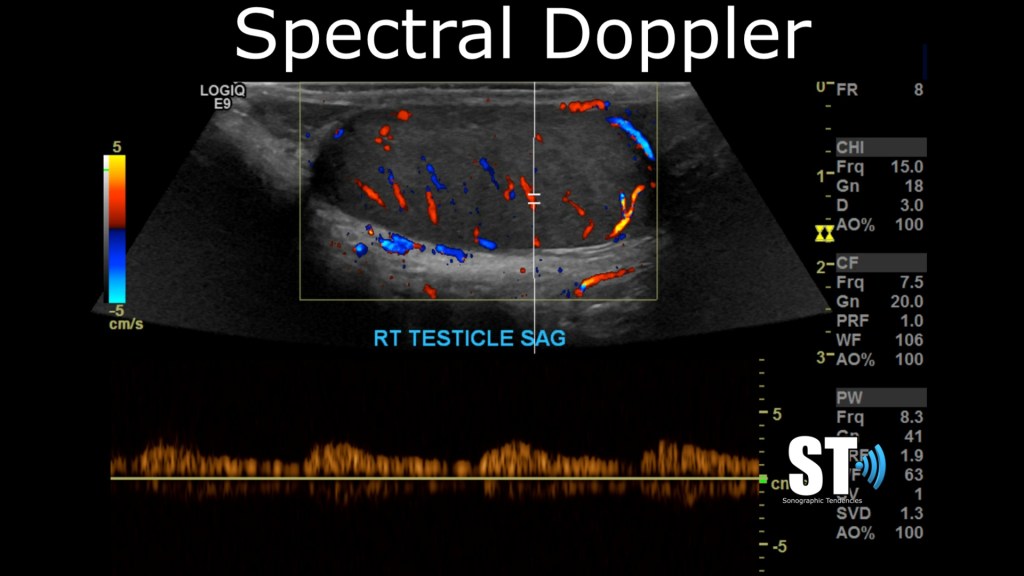

Color and Spectral Doppler

After you’re done with you sagittal grey scale images, use color and spectral doppler to interrogate the testes and take spectral tracings at the superior, mid and inferior sections of the testicle.